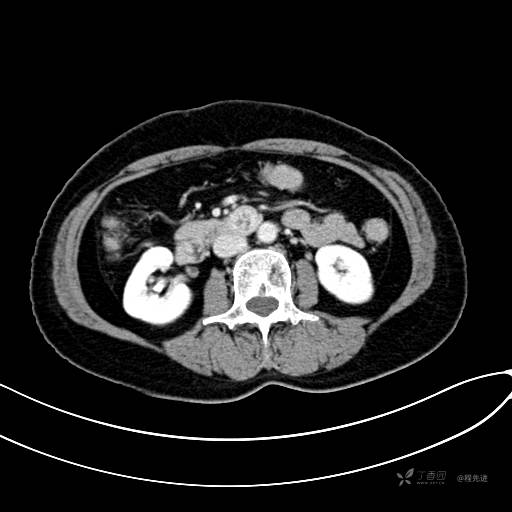

CT增强门脉期